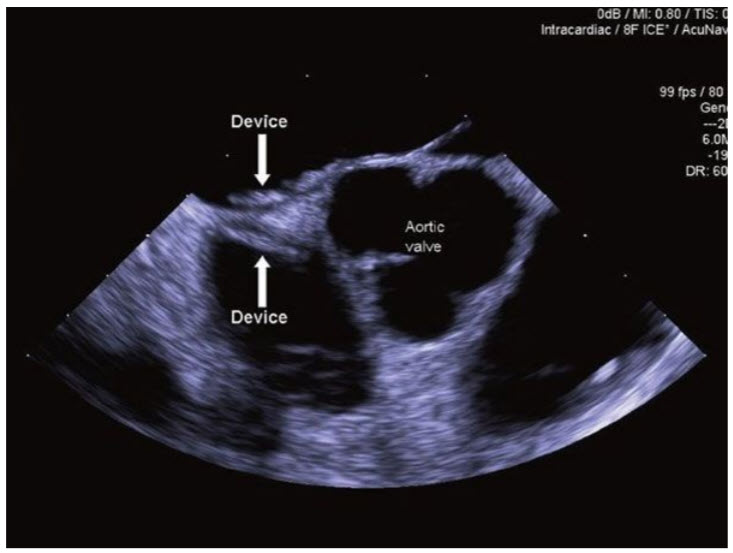

Secundum ASD. The majority of secundum ASDs can be closed with a percutaneous catheter technique. ASD closure is indicated for RA and RV enlargement with or without symptoms. Small ASDs (<5 mm) with no evidence of volume overload do not require closure unless associated with cryptogenic paradoxical embolism. Sinus venous, coronary sinus, and primum defects are not amenable to device closure (Fig. below).

An atrial septal defect (ASD) occlusion device is seen positioned across a secundum ASD. The image was acquired using intracardiac echocardiography and consists of a short-axis view of the heart demonstrating the aortic valve and the interatrial septum dividing the left atrium (LA) and right atrium (RA).